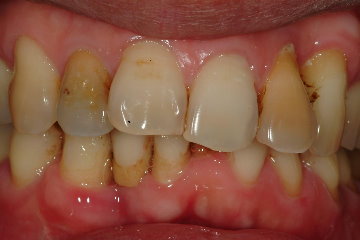

術前及術後比較

術前 |

術後 |